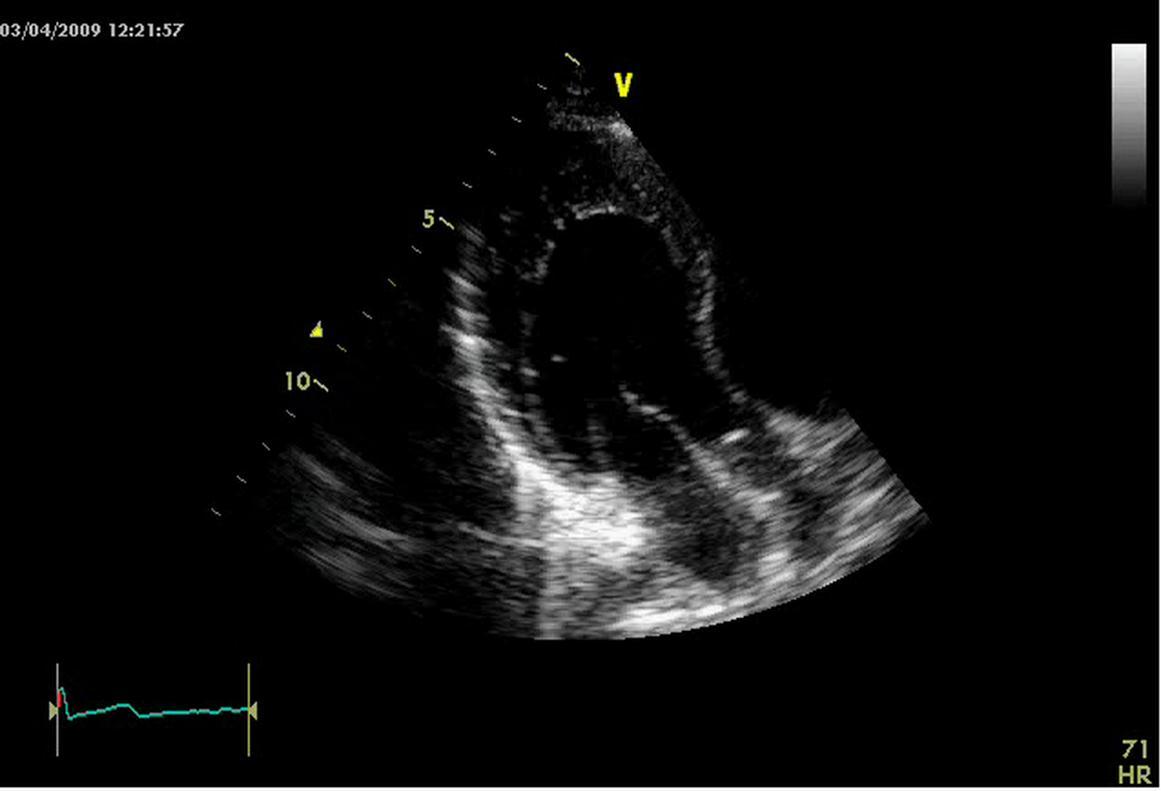

Rest electrocardiogram showed sinus tachycardia 110/m and no other anomalies. Nevertheless an ECG performed in the operatory room next day showed sinus tachycardia and a ventricular pre excitation compatible with a right anterolateral accessory pathway (Figure 1). The transthoracic echocardiogram performed in the same day demonstrated only left ventricle posterior apex, inferior and lateral wall mild thickening; furthermore, it showed two layered structure with numerous prominent trabeculae and deep intertrabecular recesses directly communicating filled with left ventricular cavity as assessed by Color Doppler. The ratio between tick non compacted layer and thin compacted part measured at end systole in short axis was > 2, according Jenni criteria for isolated left ventricular non compaction (ILVNC) (Figure 2) 1,2.

Figure 2.Echo image focused on infero-lateral apical segment of left ventricle